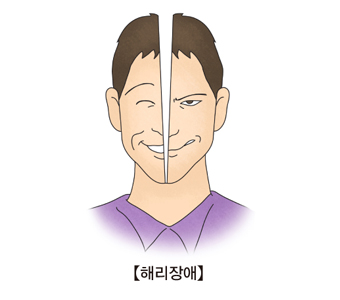

해리장애비현실감, 이인증, 정체감 혼란 및 변형, 기억장애